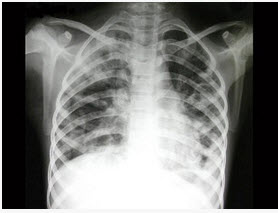

13、单项选择题

患者,女,28岁,轻咳两月,有盗汗。胸片如图:

本例最可能的诊断为()

E.肺结核

点击查看答案

14、单项选择题  在X线摄影中,使用对比剂可以增加组织间的对比,有助于形成影像。 肝肾功能严重受损不能进行静脉尿路造影检查的原因不是()

A.不能正常显影